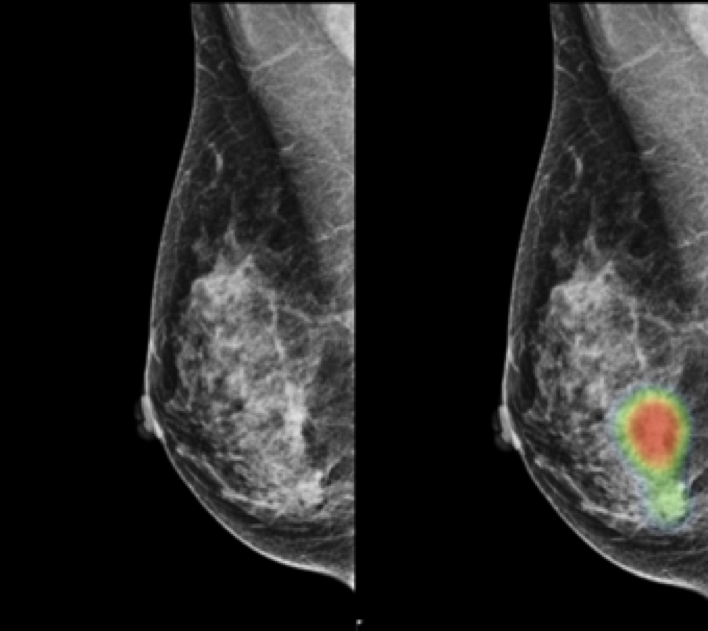

연구팀에 따르면 유방촬영 영상 판독 시 AI를 활용할 경우 영상의학 전문의의 판독 능력이 크게 향상됐다. 예를 들어 유방암 검출 정확도 측면에서 인공지능은 88.8%의 민감도를 보인 반면, 영상의학 전문의는 75.3%의 민감도를 보였다. 하지만 전문의가 AI의 도움을 받았을 때 민감도가 84.8%로 크게 향상됨을 확인할 수 있었다.

연구진은 AI 활용에 의한 판독 정확도 향상에 대해 AI가 의사 대비 특정 형태의 유방암들을 높은 정확도로 검출할 수 있었기 때문이라고 설명했다. 예를 들어 AI는 영상의학과 전문의와 비교해 종괴(mass, 90% 대 78%) 및 왜곡 또는 비대칭(distortion or asymmetry, 90% 대 50%) 형태의 유방암 검출에 있어 더욱 우수한 민감도를 보였다.

또한 AI의 높은 정확도는 진단이 어려운 조기 침윤성 유방암의 검출에 더욱 뛰어났다. 영상의학 전문의의 경우 T1 암 및 림프절 비전이 암 각각에 대해 74%의 민감도를 보인 반면, AI는 각각 91% 및 87%의 민감도를 보였다.

논문에 따르면 AI의 진단 성능은 유방 밀도의 영향을 덜 받은 반면, 영상의학과 전문의는 밀도에 영향을 크게 받았다. 치밀 유방에 대한 전문의의 민감도는 73.8%로, 치밀 유방이 아닌 경우에 대한 민감도 79.2%보다 현저히 낮았다. 하지만 AI의 도움을 받을 경우, 전문의의 치밀 유방 판독 민감도가 85.0%로 크게 향상됐다.